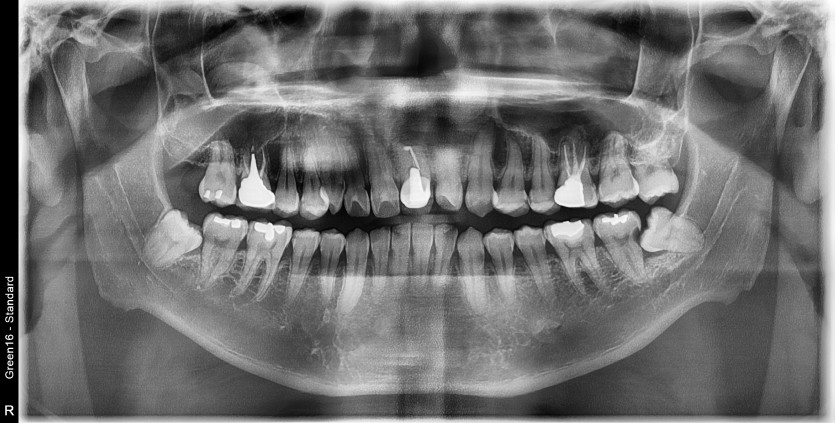

#48 사랑니 발치

구강 외과 전문의가 당일 발치했습니다.